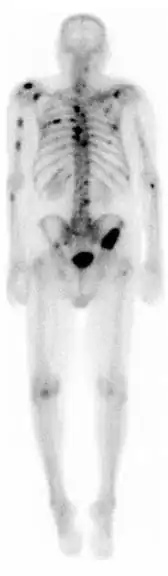

Gammagrafía ósea

Una gammagrafía ósea es una prueba de medicina nuclear para encontrar ciertas anormalidades en los huesos. Se utiliza sobre todo para ayudar a diagnosticar: cáncer de los huesos o cáncer que se ha diseminado (metástasis) hasta el hueso, la localización de algunas fuentes de inflamación en los testículos (por ejemplo, dolor óseo, tales como dolor de espalda debido a una fractura), el diagnóstico de las fracturas que pueden no ser visibles en las tradicionales imágenes de rayos X, y la detección de daños en los huesos debido a ciertas infecciones y otros problemas.

En general, lo que se busca con esta prueba diagnostica son imágenes de hipercaptación que pueden ser localizadas, múltiples o difusas. Cuando son difusas recibe el nombre de superscan. Las imágenes de hipocaptación son más raras. El aumento de captación ósea puede ser por cuatro motivos: el aumento de la formación osteoide, una mineralización ósea aumentada, un aumento de la vascularización, del flujo sanguíneo, o por una denervación simpática.

La técnica en sí consiste en la administración intravenosa de 10-20 milicurios de 99mTc-MDP (Metilén difosfonato) o de 99mTc-HEDP (Hidroxi-Etilén-difosfonato). Tras 2-5 horas postinyección se realiza la adquisición de las imágenes de cuerpo entero, que se llama rastreo anterior y rastreo posterior. Eventualmente, estos rastreos de cuerpo entero se pueden complementar con: gammagrafías localizadas de huesos concretos, SPECT muy útil en columna vertebral y pelvis o gammagrafía ósea de tres fases.